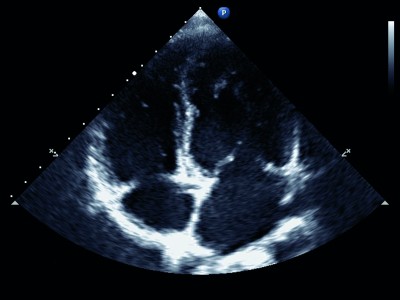

Echo (echocardiogram) – this is a type of ultrasound scan, which uses sound waves to create echoes when they hit different parts of the body. These echoes are translated into 2- and 3- dimensional images. This test looks at the structure of the heart, and are used to see if the heart is enlarged or if there is any thickening of the heart muscle. The images are moving, so can also look at how the heart is working. A Doppler echo looks at the speed and flow of blood through the heart, which also helps to check how the heart is working.